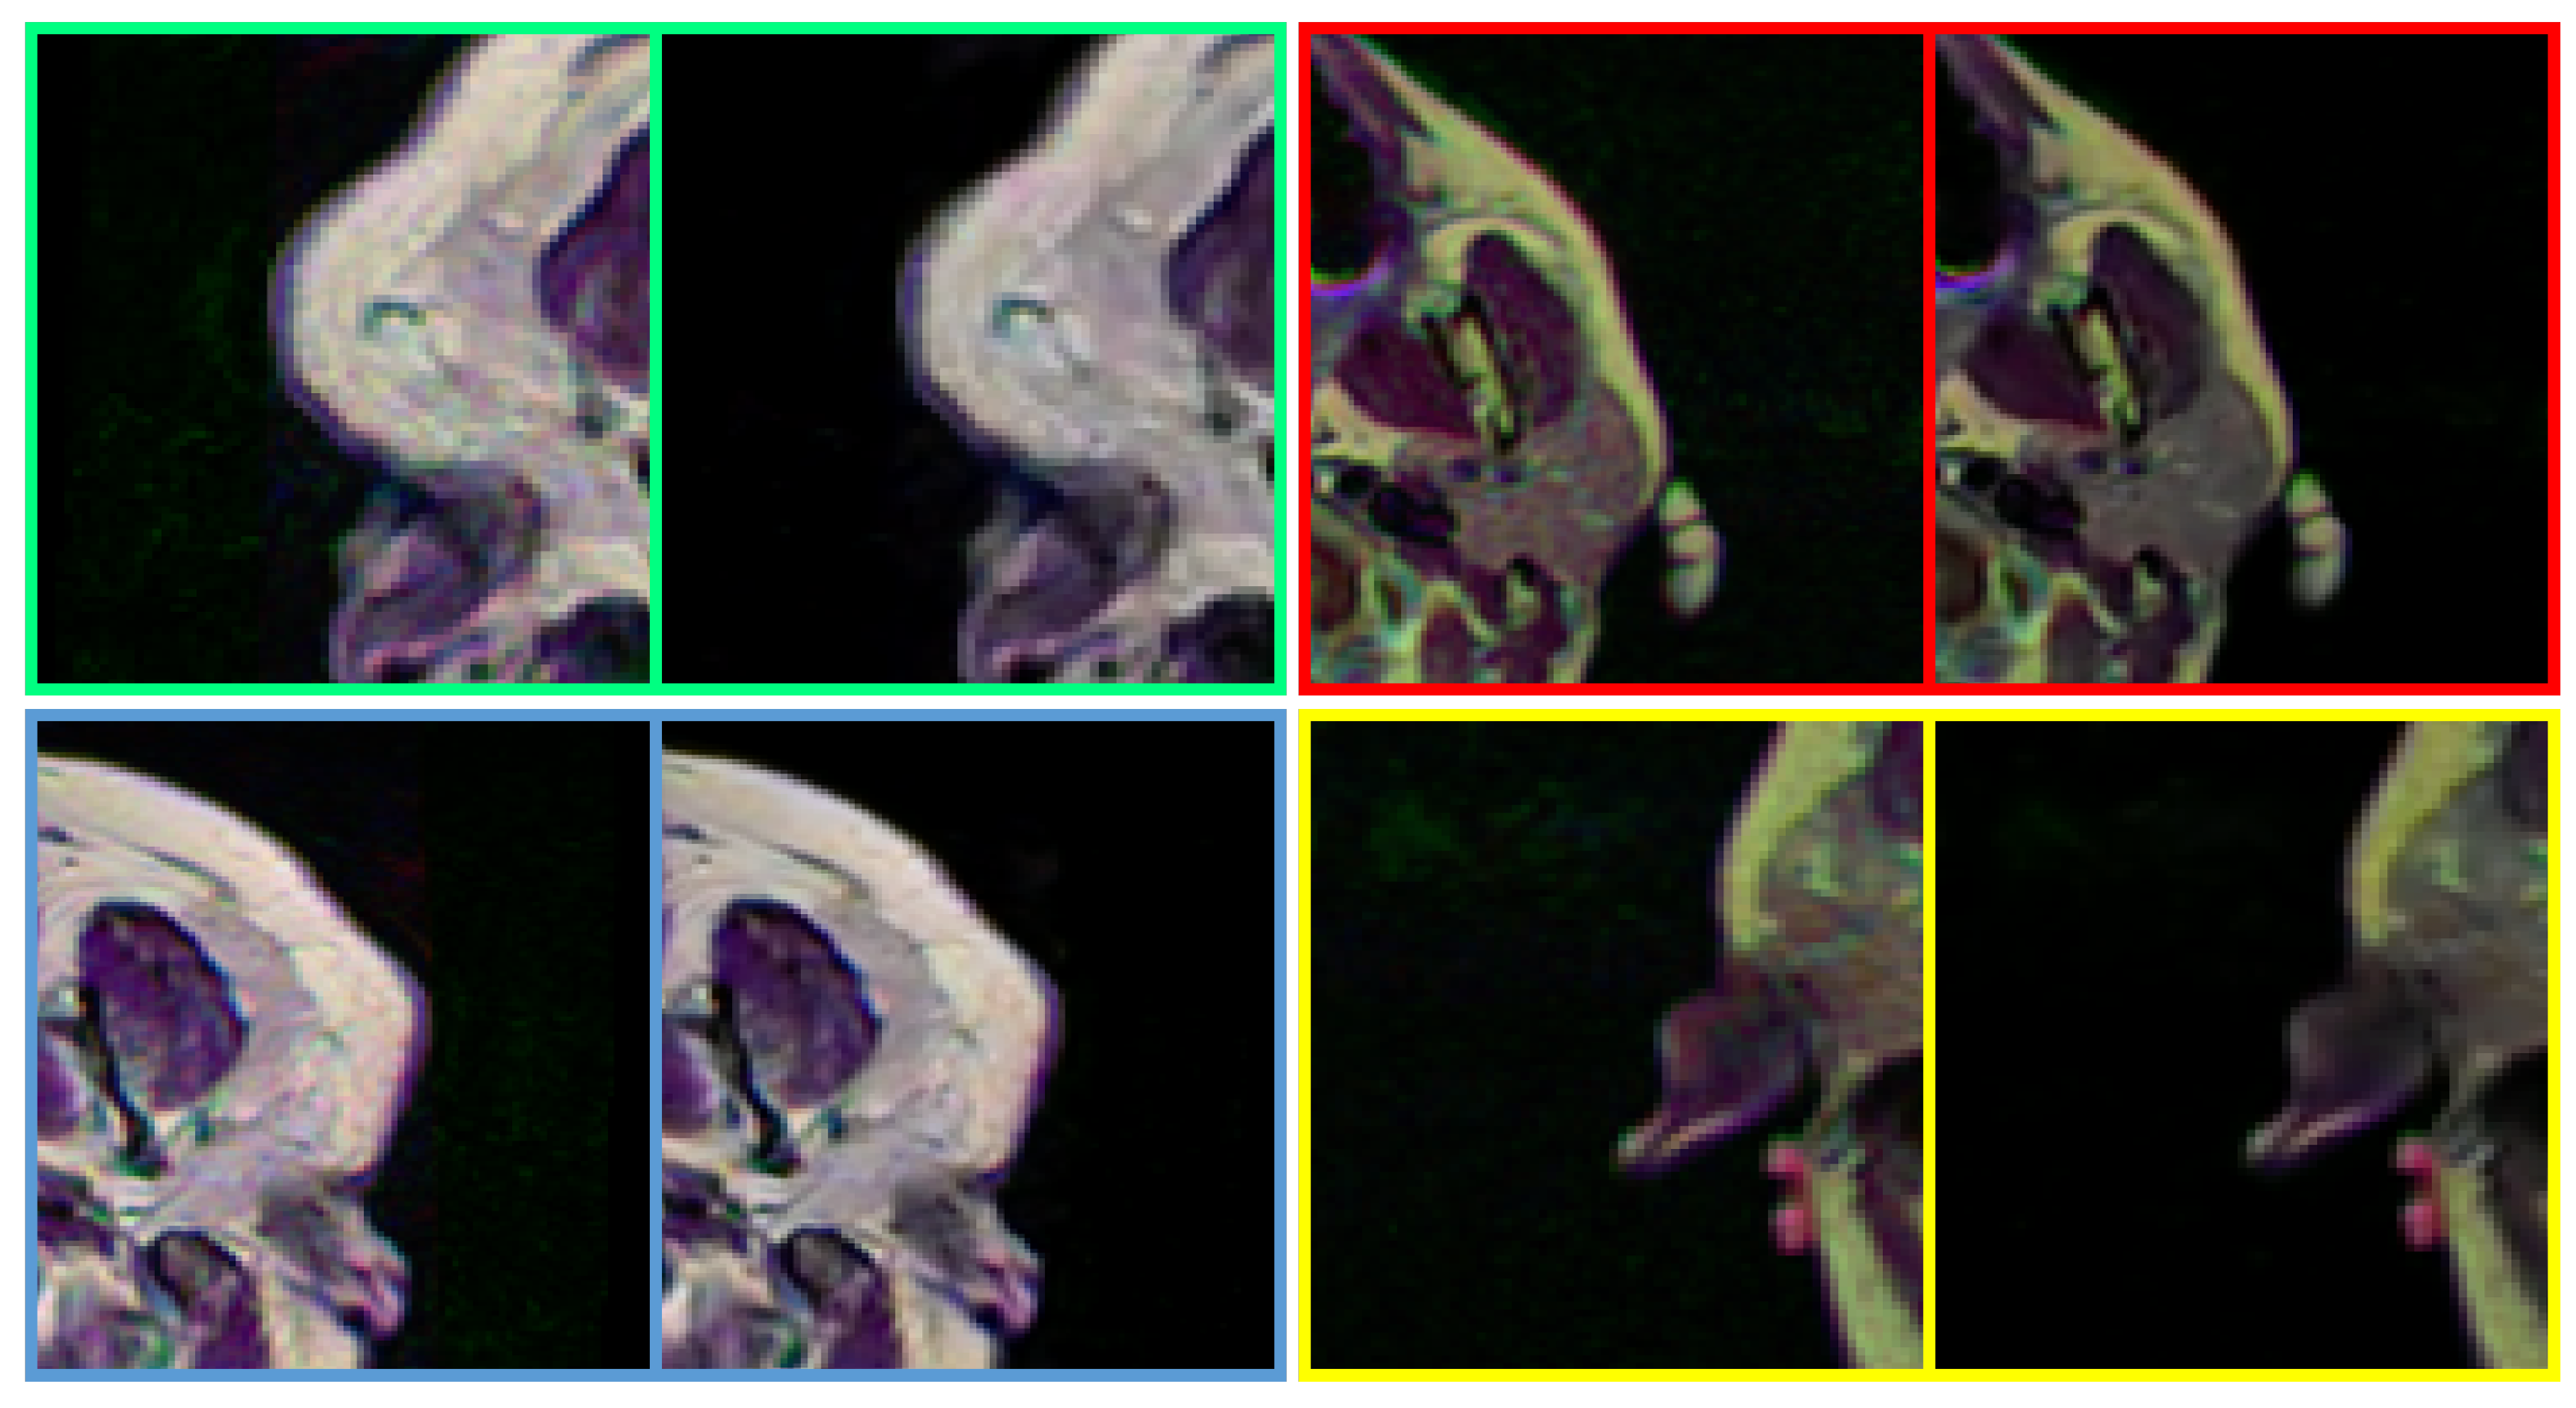

4.2. Real-World Noise Removal

In the real-world scenario, the noise that appeared in the medical images can differ from the synthesized data. Therefore, to push the MID a furthermore, the feasibility of the proposed method has been studied with real-world noisy medical images. As Figure 8 illustrates, the proposed method can notoriously handle the real-world noise and substantially improve the perceptual image quality of noisy medical images by removing blind-fold noise.

Figure 8. Performance of the proposed method in removing noise from real-world medical images. The proposed method can handle real-world noise without producing any visually disturbing artefacts. In each pair, left: Noisy input, Right: Denoised image (obtained by DRAN). Source by: (https://www.kaggle.com/mateuszbuda/lgg-mri-segmentation).